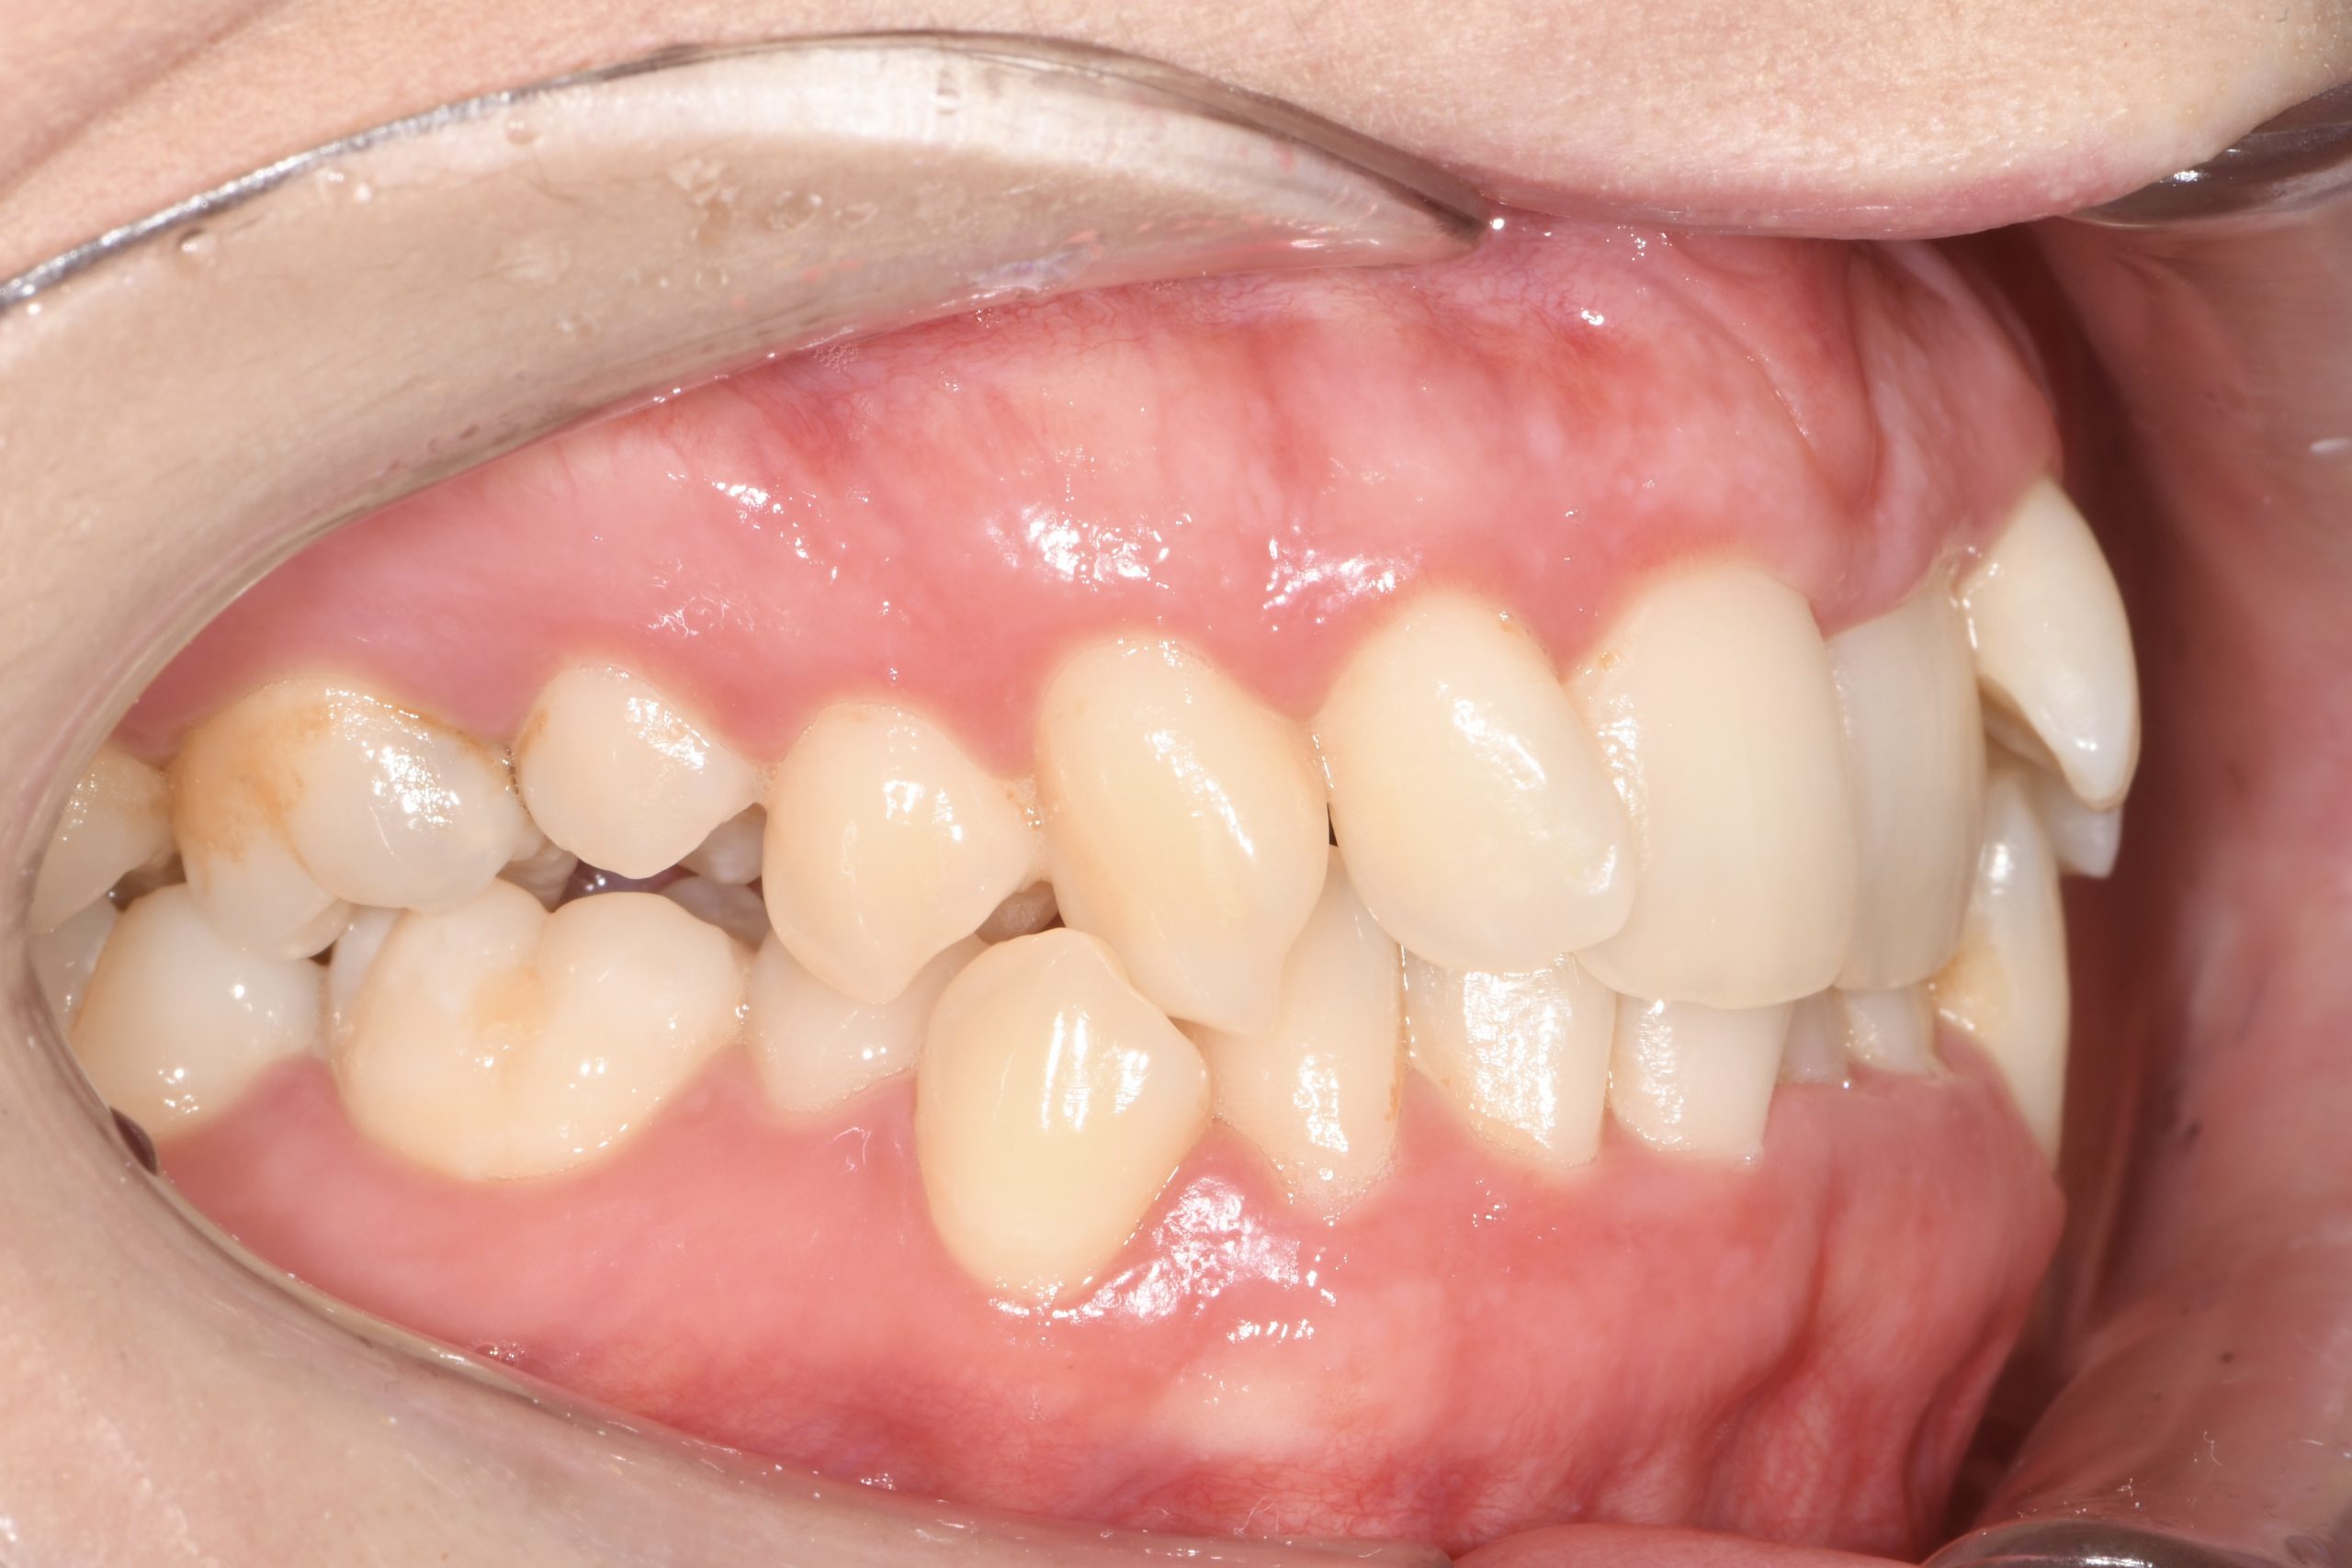

Az elmúlt évekből rengeteg szakmai referenciát tudnánk bemutatni, amelyek különböző fogszabályozási problémákat oldottak meg. Válogatva a több száz esetből, ezen az oldalon olyan képeket, információkat igyekeztünk bemutatni, amelyeknek a segítségével a jövőbeni pácienseinknek azt tudjuk üzenni: A Te fogsorod is lehet gyönyörű!

(Képeket a Pácienseink külön írásos beleegyezésével mutatjuk be!)